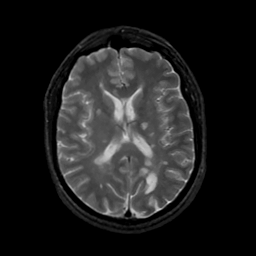

MR Study #13, May 19, 1991 -- Slice #29